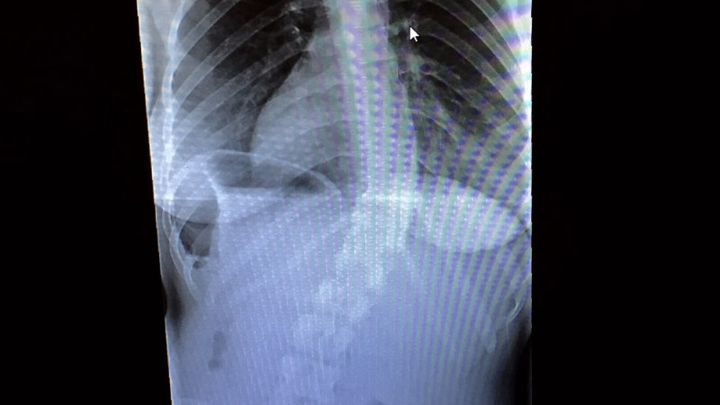

As some of you may know, Allyn has had severe scoliosis her entire life. Six years ago it was discovered that she had a 32 degree curve on her spine. Two months ago she had more x-rays taken along with MRIs that showed an increase in the curve to 47 degrees, making it a mandatory surgery. Though she may seem fine from her appearance, this degree of scoliosis is extremely painful which makes it difficult to go about her day to day activities.